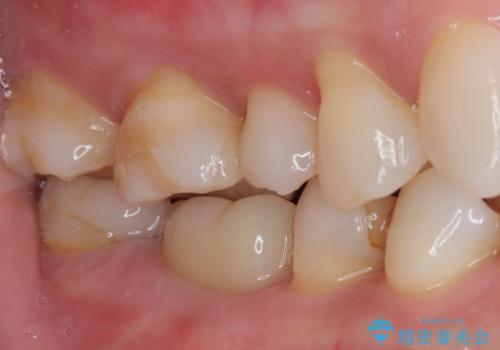

- 今回は、「右上の詰め物が欠けてしまった」という主訴で来院された、40代女性の患者さんの症例をご紹介します。

診察の結果、上顎右側第二小臼歯に装着されていた詰め物の一部が欠けている状態でした。一見すると小さな欠けに見えますが、詰め物が破損した部分はプラーク(歯垢)が非常に溜まりやすく、虫歯の再発リスクが高い状態になります。

まず、欠けていた詰め物と、その下に存在していた虫歯をすべて丁寧に除去しました。その後、適合性・耐久性・審美性に優れたセラミックインレーを用いて修復処置を行いました。